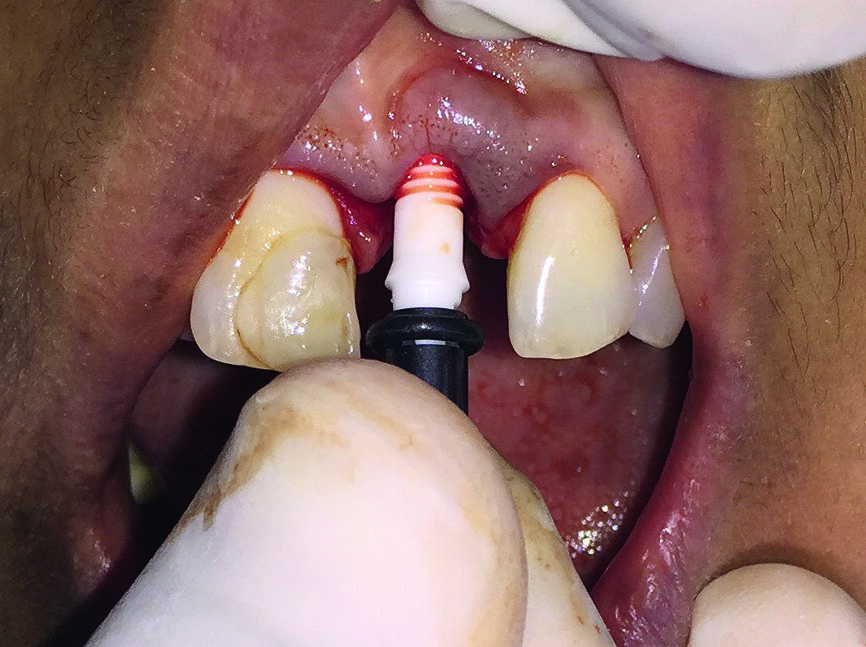

L’extraction atraumatique de la dent 21 a été réalisée au moyen d’un périotome, sous anesthésie locale (lidocaïne – Lignox, Indoco –, avec adrénaline 1:200 000) (Fig. 2). Des curettes à os ont été utilisées pour débrider complètement l’alvéole d’extraction, afin d’éliminer le tissu de granulation. L’étape suivante a consisté à préparer les sites de l’ostéotomie au moyen d’un foret guide et le tout a été vérifié avec des indicateurs de direction. Le forage a ensuite été accompli jusqu’à une longueur correspondant précisément à celle de l’implant et un implant ZiBone en zircone (Ø 4,0 mm, longueur 12,0 mm) a été inséré en position 21.

Un couple d’insertion d’environ Ncm a été utilisé pour obtenir la stabilité primaire (Figs. 3a–c).

Figs. 3a–c : Implant ZiBone monobloc en zircone (Ø 4,0 mm, longueur 12,0 mm).